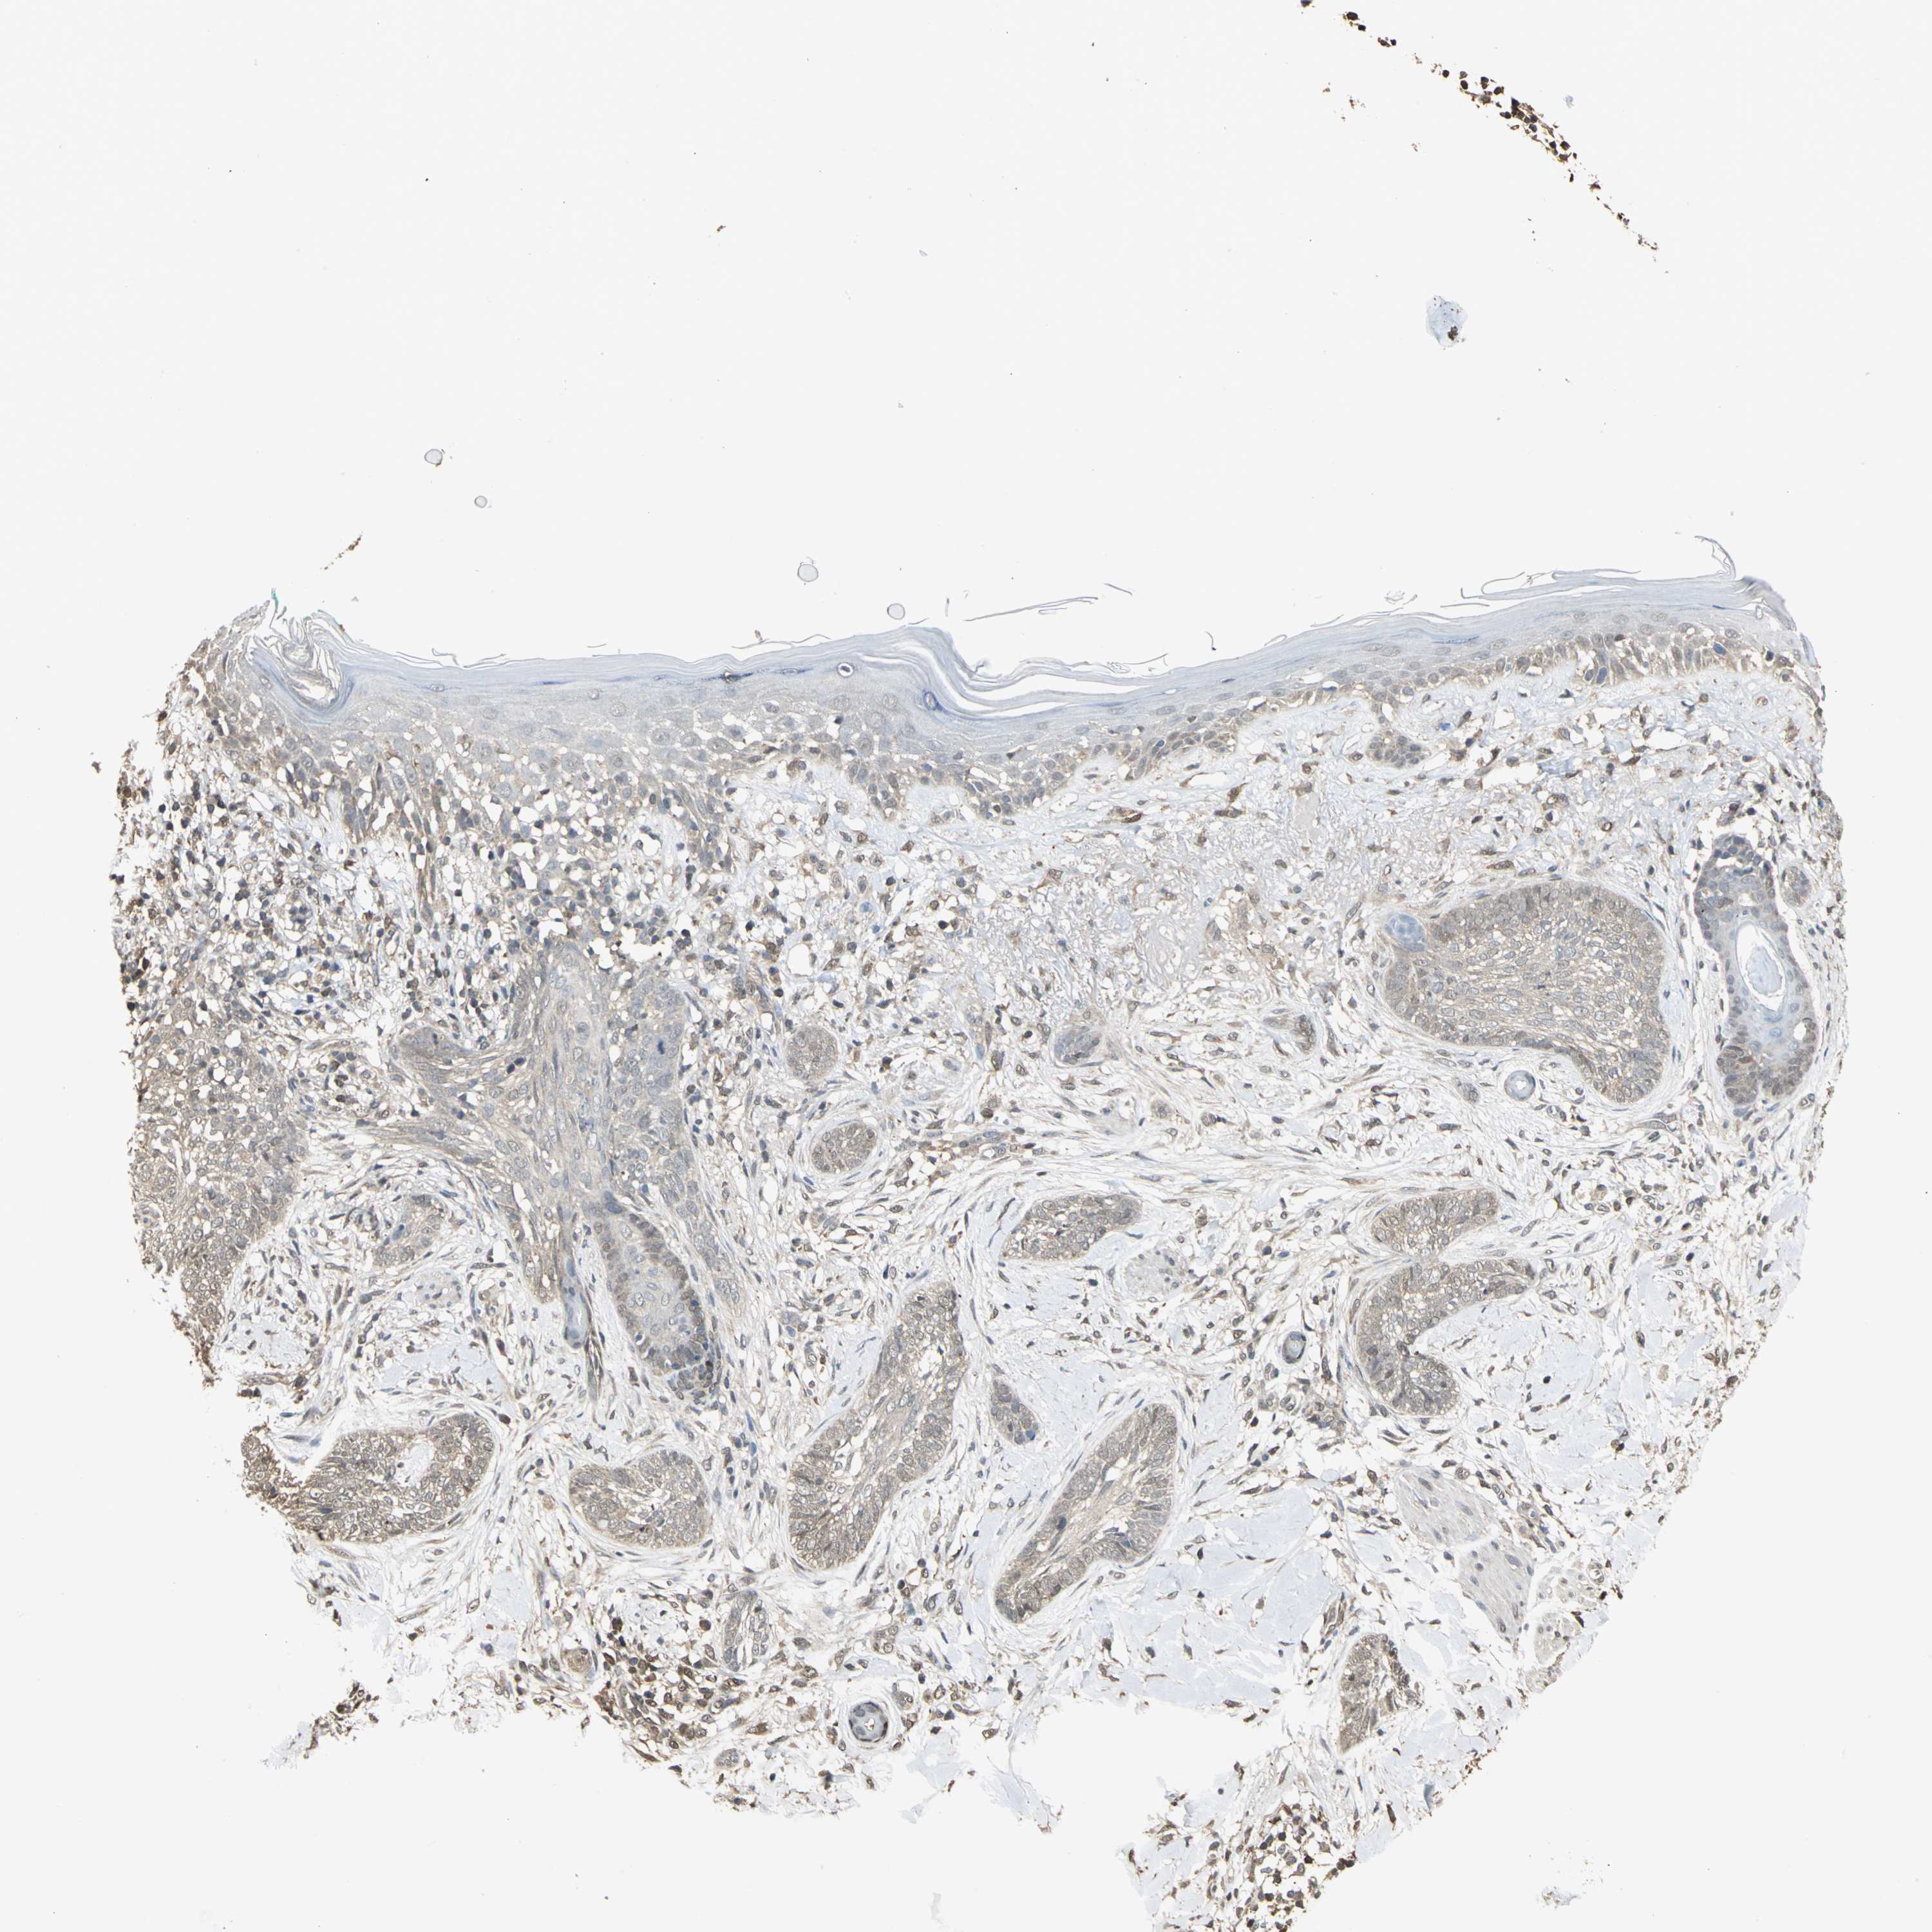

Basal cell and squamous cell cancer

SKIN CANCER - Protein expressioni

A mouse-over function shows sample information and annotation data. Click on an image to view it in a full screen mode. Samples can be filtered based on level of antibody staining by selecting one or several of the following categories: high, medium, low and not detected. The assay and annotation is described here.

Antibody stainingi

Antibody staining in the annotated cell types in the current human tissue is reported as not detected, low, medium, or high, based on conventional immunohistochemistry profiling in selected tissues. This score is based on the combination of the staining intensity and fraction of stained cells.

Each image is clickable and will lead to virtual microscopy that enables deeper exploration of all samples and also displays staining intensity scores, fraction scores and subcellular localization as well as patient and tissue information for each sample.

Antibody HPA004190

Antibody CAB005870

Squamous cell carcinoma, NOS

Basal cell carcinoma